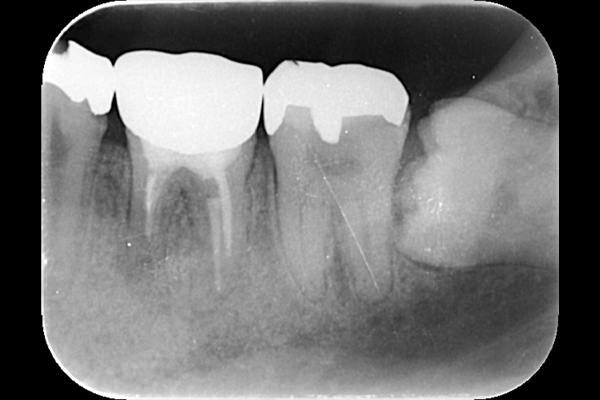

それは歯の先に枝分かれが多く存在し、そこにばい菌が入り込んで難治性となっているからです。ではその場合どうするのか?外科治療をします。その枝分かれの部分を切り落とすのです。今回はその前後のレントゲンの写真をお見せします。

| 根の中の薬が十分に充填されておらず、根の先が周りと比べて黒くなっており、炎症があると判断できます。 | 根の中にしっかりとお薬を緊密に充填しましたが、まだ根の先に黒くなっている部分があります。 |